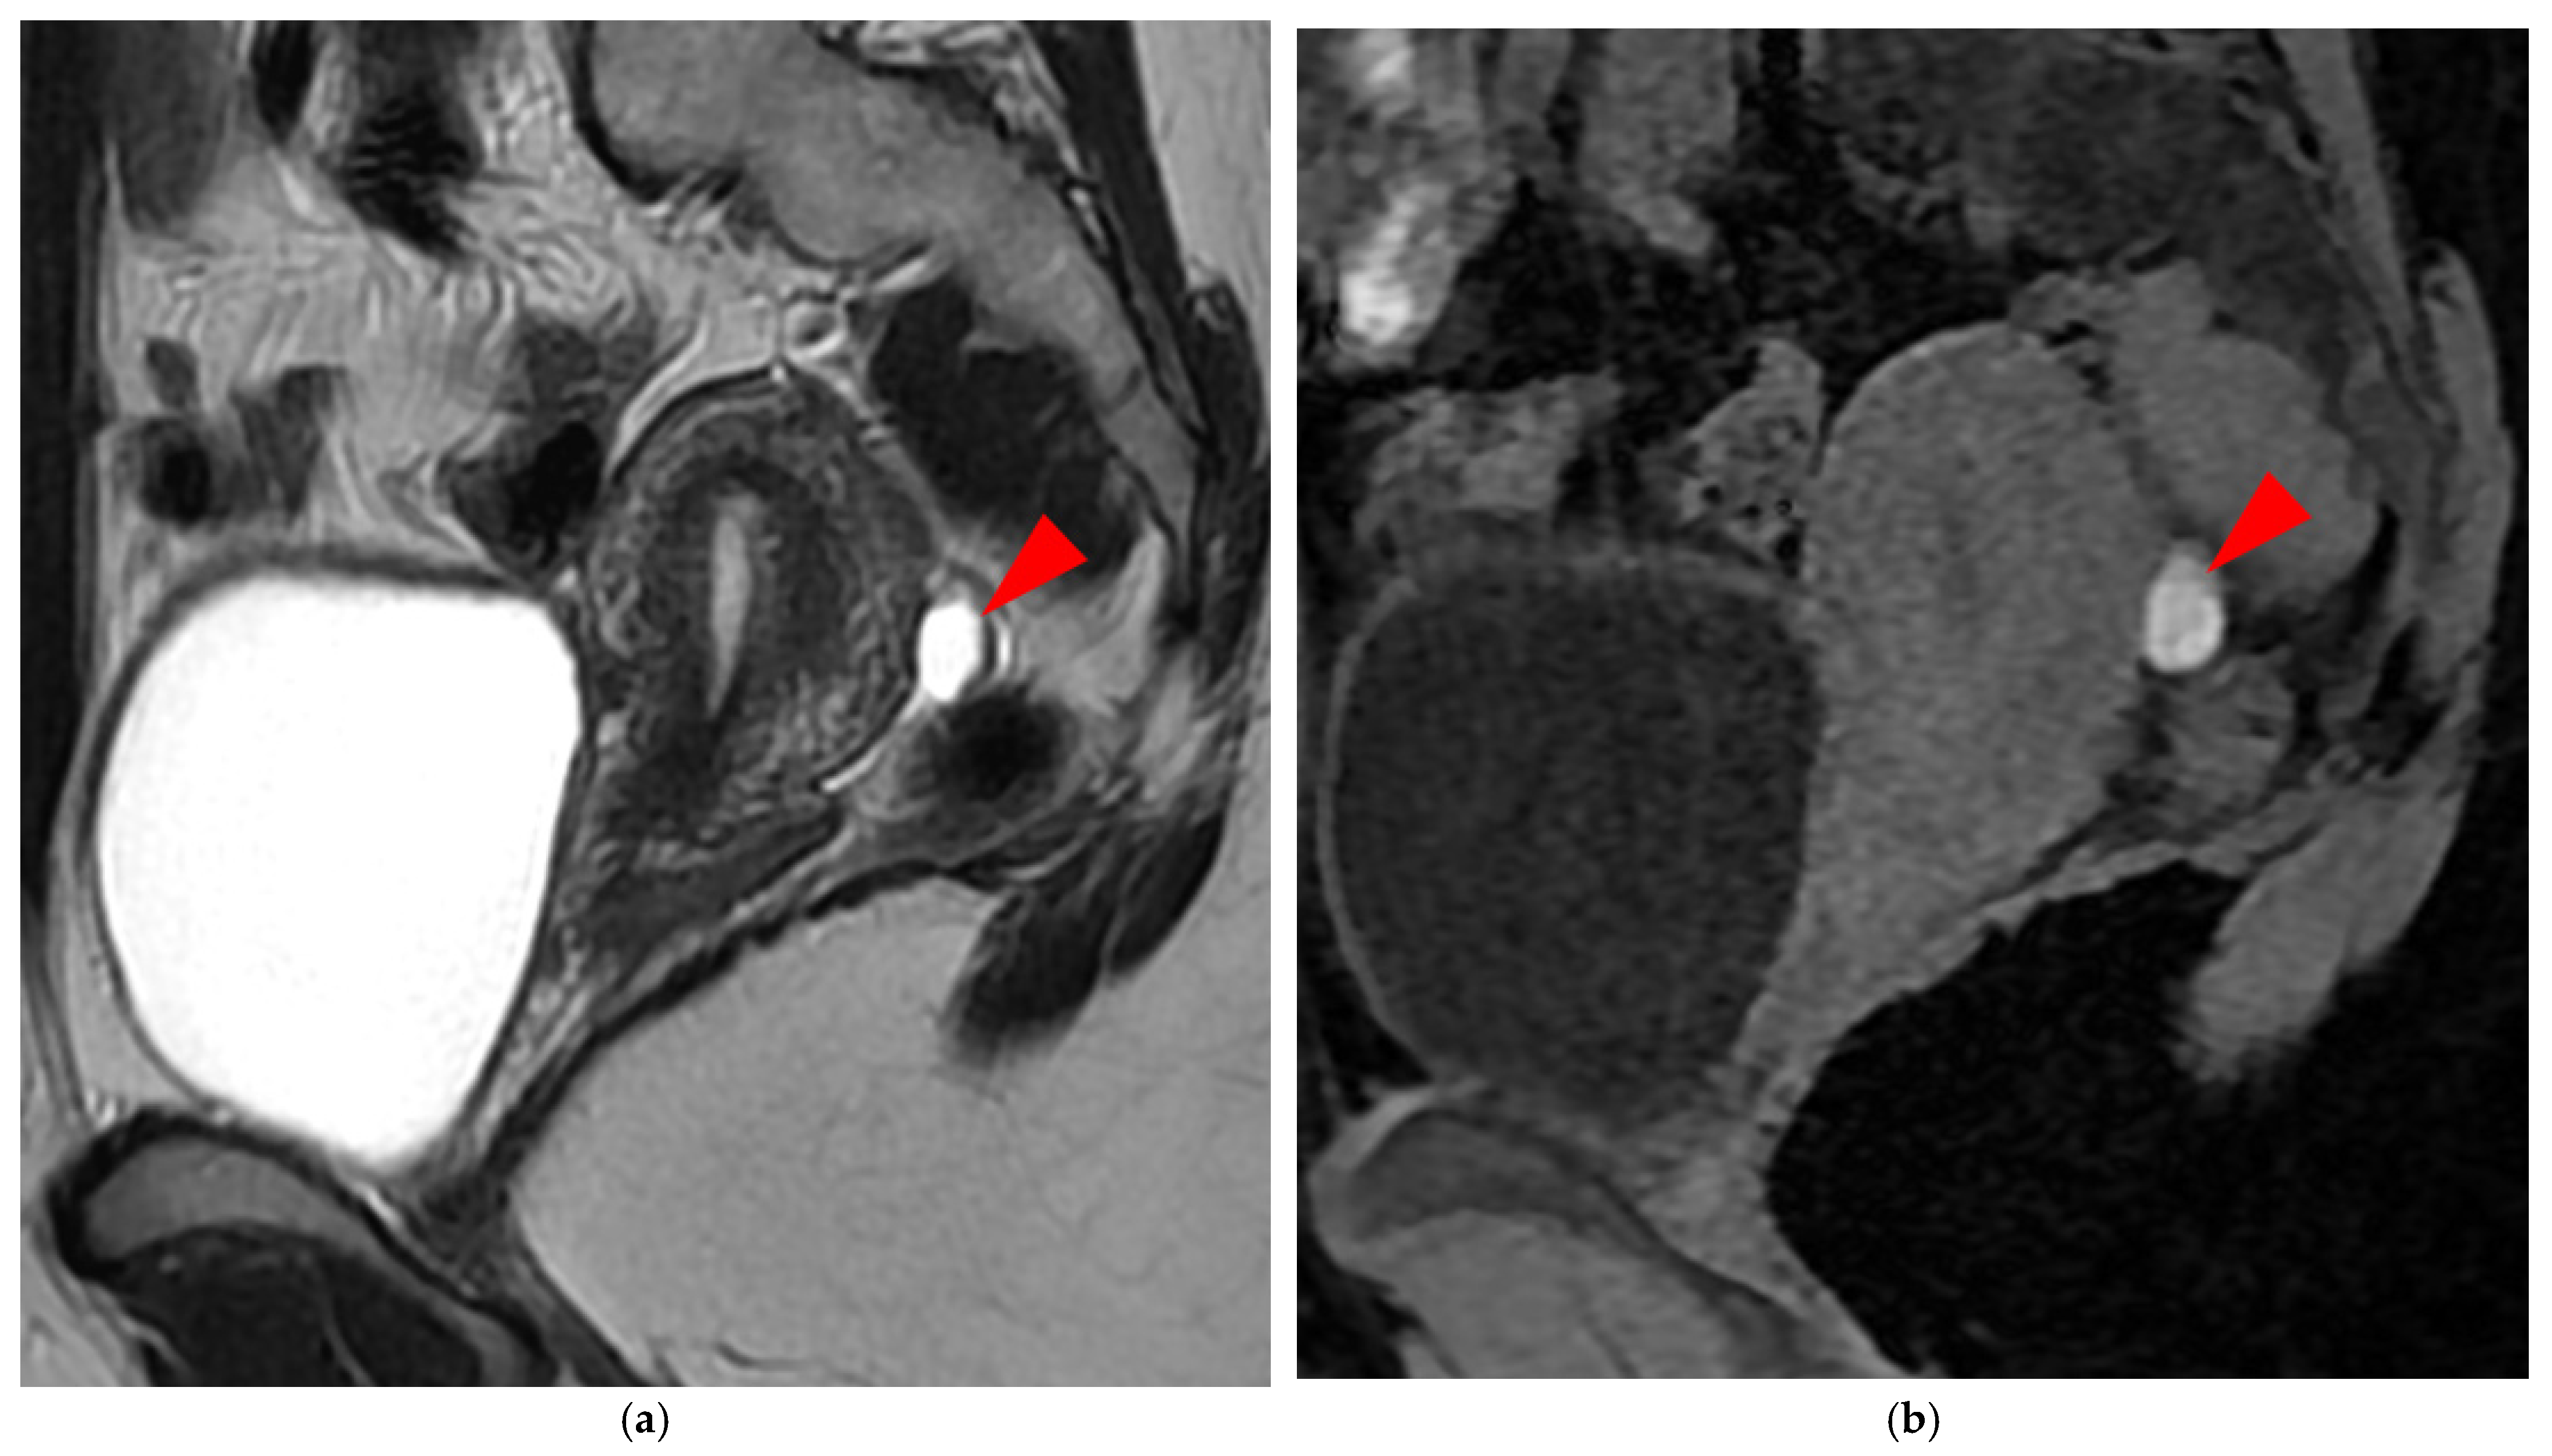

2.2.1. HTD Type 4 USL (PPV = 100%; FPR = 0%)

A type 4 USL (Figure 5) contains hemorrhagic implants, visible on MRI as hyperintense spots on fat-suppressed T1WI.

Figure 5. Pelvic MRI scans of two patients with HTD type 4 USLs. (a,b) Patient 1—(a) Axial T2WI: a focally thickened right proximal USL (arrowhead) with caliber disparity, initially classified as a type 3B USL. (b) Axial fat-suppressed T1WI: a hyperintense hemorrhagic spot (arrowhead) within this thickened right proximal USL, ultimately reclassifying it as a type 4 USL. Note the typical hyperintense right ovarian endometrioma (red star). (c,d) Patient 2—(c) Sagittal T2WI: a visible but thin (1.5 mm) left USL (arrowhead), initially classified as a type 2 USL. (d) Sagittal fat-suppressed T1WI: a hyperintense hemorrhagic spot (arrowhead) at the origin of this USL, ultimately reclassifying it as a type 4 USL.